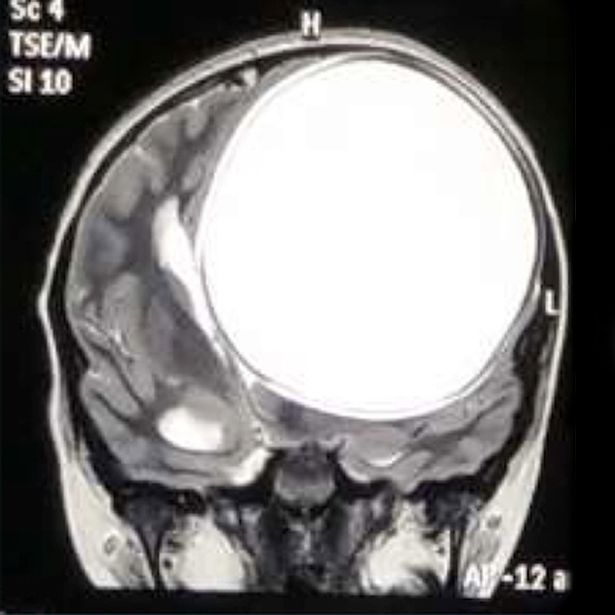

Τη μεγαλύτερη κύστη που έχει αφαιρεθεί στην Ιστορία της ιατρικής! Ζύγιζε 675 γραμμάρια, ενώ είχε διαστάσεις 12.2cm x 11cm x 9.8cm!

«Πιστεύω ότι μεγάλωνε μέσα στο κεφάλι της από όταν ήταν 10 ετών και είχε φθάσει σε μέγεθος το μισό του εγκεφάλου της. Θα μπορούσε να σκάσει ανά πάσα στιγμή και να τη σκοτώσει», αποκάλυψε από την πλευρά του ο Dr Solanki, ο οποίος ανέλαβε να χειρουργήσει (με επιτυχία και για 2,5 ώρες) τη μικρή, για να προσθέσει: «Παραδέχθηκαν ότι δεν ζούσαν σε υγιεινό περιβάλλον και αυτός είναι ο λόγος που η Nita προσβλήθηκε από το παράσιτο».